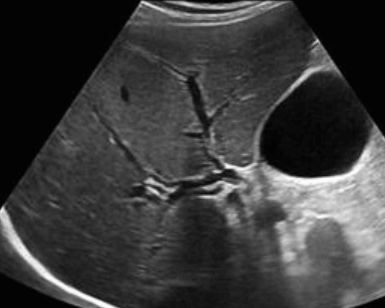

- 간외담관(extrahepatic bile duct)은 총 간관(CHD)과 총담관(CBD)으로 나뉘고 그 끝은 십이지장 내 유두부이다.

extrahepatic bile duct 3) 지방식 (fatty meal)